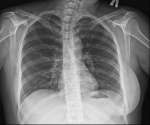

Пол пациента: Женский пол Тип патологии: Другое Область исследования: Скелетно-мышечная система Методы исследования: Rg Вот такая девушка пришла с некпонятными болями в ОГК. Смущает грудинный конец ключицы, норма ли это? ID:72948 Цель публикации: Консультация Сб, 02/09/2017 - 10:33 #1 DrMaximova Не на сайте Был на сайте: 3 года 5 месяцев назад Зарегистрирован: 25.11.2012 - 17:38 Публикации: 287 Простите, что изображения не перевернуты. Загружала нормально Сб, 02/09/2017 - 11:20 #2 И.Бондаренко Не на сайте Был на сайте: 1 день 9 часов назад Зарегистрирован: 13.09.2011 - 22:55 Публикации: 9209 Нориально. Только в рёберно-позвонковых суставах Th 9 и 10 слева есть остеофиты - дефартроз. Сб, 02/09/2017 - 11:43 #3 DrMaximova Не на сайте Был на сайте: 3 года 5 месяцев назад Зарегистрирован: 25.11.2012 - 17:38 Публикации: 287 И.Бондаренко wrote: Нориально. Только в рёберно-позвонковых суставах Th 9 и 10 слева есть остеофиты - дефартроз. А покажите из пожалуйств Сб, 02/09/2017 - 11:48 #4 DrMaximova Не на сайте Был на сайте: 3 года 5 месяцев назад Зарегистрирован: 25.11.2012 - 17:38 Публикации: 287 Еще стрелкой это тоже остеофит? Приложения: Сб, 02/09/2017 - 12:29 #5 И.Бондаренко Не на сайте Был на сайте: 1 день 9 часов назад Зарегистрирован: 13.09.2011 - 22:55 Публикации: 9209 Вот так Приложения:

Нориально. Только в рёберно-позвонковых суставах Th 9 и 10 слева есть остеофиты - дефартроз.